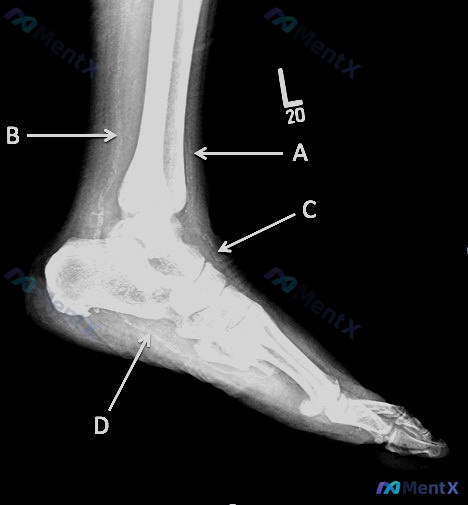

整理了一份影像资料,结合两个维度想和大家讨论: 首先是纯解剖识别问题——这份踝关节及足部侧位X光片里,箭头C标识的是哪条动脉? 然后补充一下影像里的其他发现,供大家参考: 1. 骨骼:未见明确骨折、脱位或骨质破坏 2. 软组织:有多个区域异常——踝前部肿胀、Kager三角区密度增高、足背侧肿胀、足底...